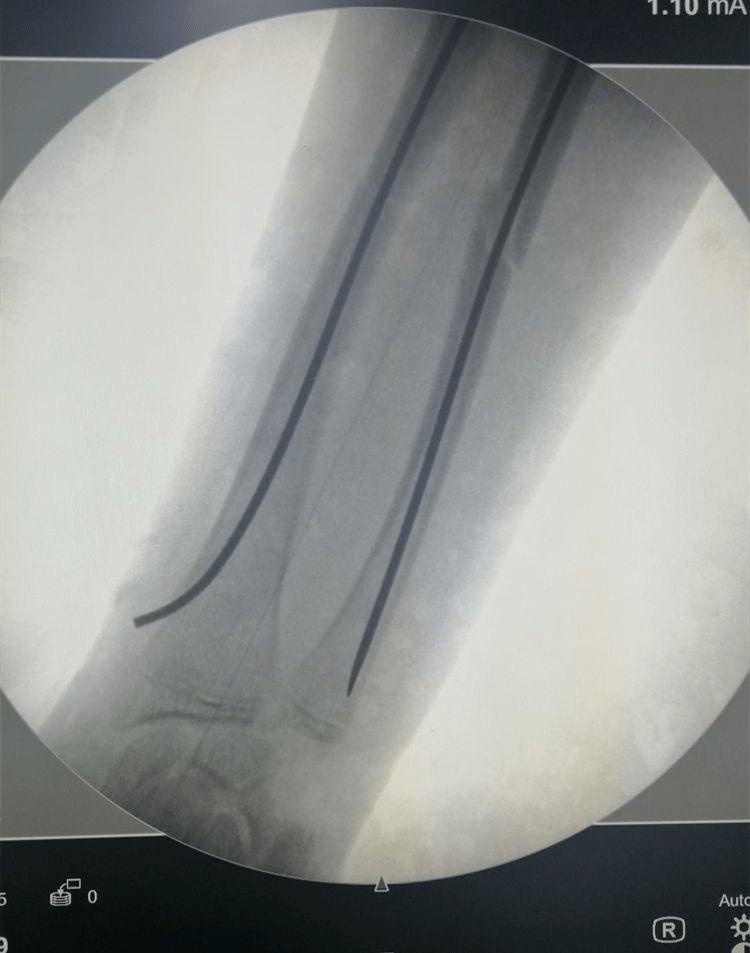

2枚直径2.5mm弹性髓内针内固定.手术切口分别为1cm和0.5cm

儿童股骨干骨折,弹性髓内针固定